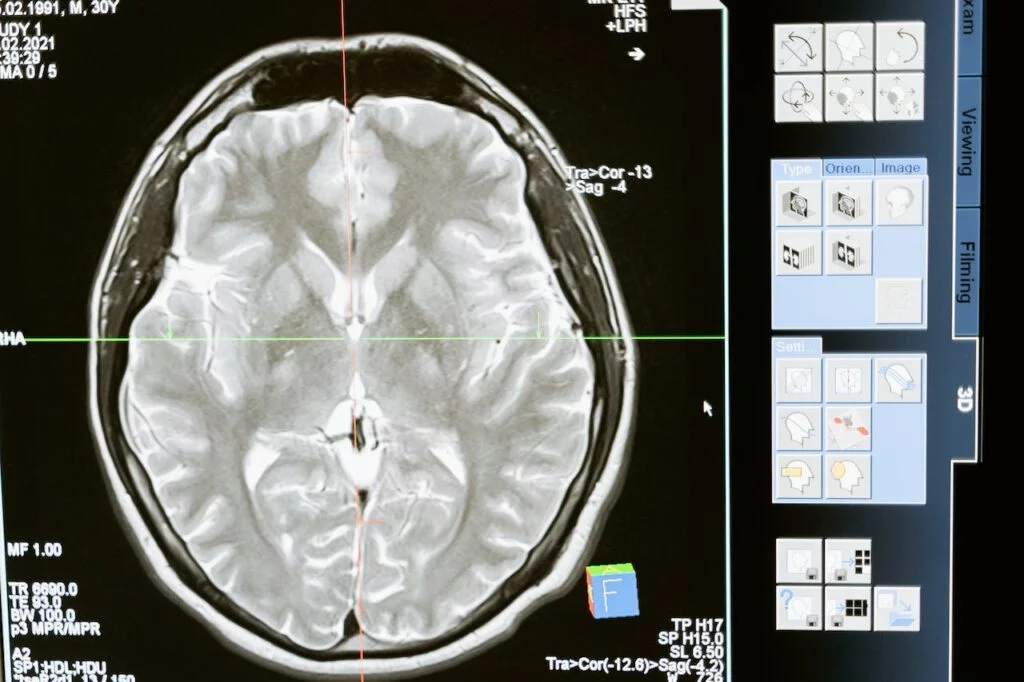

I ricercatori dell’Università del Michigan hanno creato un sistema di imaging cerebrale unico che catturerà l’attività neuronale con una risoluzione mai vista prima. Ciò aprirà nuove possibilità per studiare i processi di formazione e riproduzione della memoria, nonché per identificare le cause dei disturbi della memoria associati a malattie come il morbo di Alzheimer.

Le attuali tecniche di imaging cerebrale catturano solo poche centinaia di singoli neuroni, le cellule nervose che trasmettono segnali elettrici in tutto il corpo. Il nuovo sistema ha il potenziale per catturare da 10.000 a 20.000 neuroni contemporaneamente, offrendo ai ricercatori una visione senza precedenti dell’attività cerebrale in tempo reale.